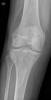

APR Gonartrosis